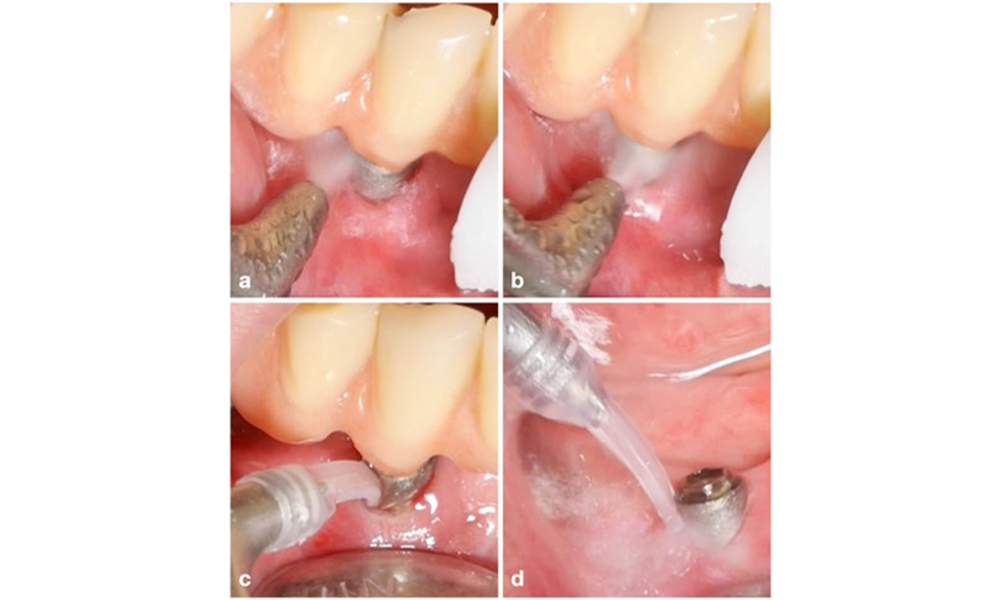

Management of peri-implantitis at implants judged as treatable consists of a non-surgical phase, which is often followed by surgical intervention. For the non-surgical approach, similar measures as those applied for the treatment of peri-implant mucositis are used; based on laboratory experiments air-polishing devices with a subgingival nozzle appear to provide certain advantages in terms of biofilm removal, compared to hand- or ultrasonic instruments (Herrera et al. 2023; Moharrami et al. 2019; Ronay et al. 2017) (figure 9).

Patient case with peri-implantitis. The non-surgical treatment is performed by using the supragingival (a-b) and subgingival handpiece of an air-polishing device (c-d). Removing the supra-construction provides better access to the implant surface (d).

Figure 9. Patient case with peri-implantitis. The non-surgical treatment is performed by using the supragingival (a-b) and subgingival handpiece of an air-polishing device (c-d). Removing the supra-construction provides better access to the implant surface (d).

Yet, the non-surgical approach often has limitations in accessing the implant surface, leading to insufficient decontamination. This is indeed reflected in the clinic, where disease resolution after non-surgical treatment of peri-implantitis is rather unpredictable and recurrence is observed for most cases, i.e., disease resolution was reported to occur only in less than every second case (Ramanauskaite et al. 2021). Therefore, the outcome of non-surgical treatment needs to be evaluated after about 6 weeks, and in cases of moderate or advanced peri-implantitis, surgery should be expected.